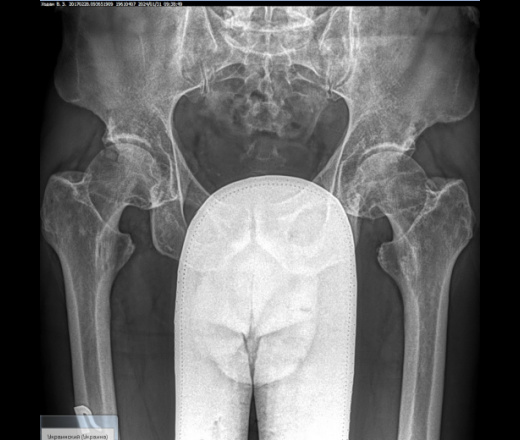

Foot and ankle orthopaedic surgeons typically diagnose talar avascular

necrosis through X-rays and/or MRI. X-rays should be weightbearing (taken while you are standing) to enable your surgeon to better evaluate the alignment of your bones. Weightbearing X-rays also allow your surgeon to identify narrowing of the joint

spaces around the talus, which is a sign of arthritis (loss of

joint cartilage that can cause pain and stiffness).

An MRI can show exactly how much of the bone is affected, and how much damage there may be to the cartilage in the joints around the talus. CT scans can also be helpful to identify any associated fractures or fragmentation of the bone.

An MRI image showing talar avascular necrosis with fragmentation and collapse. The green arrow points to the healthy bone of the tibia, while the red arrow points to the dead bone of the talus.